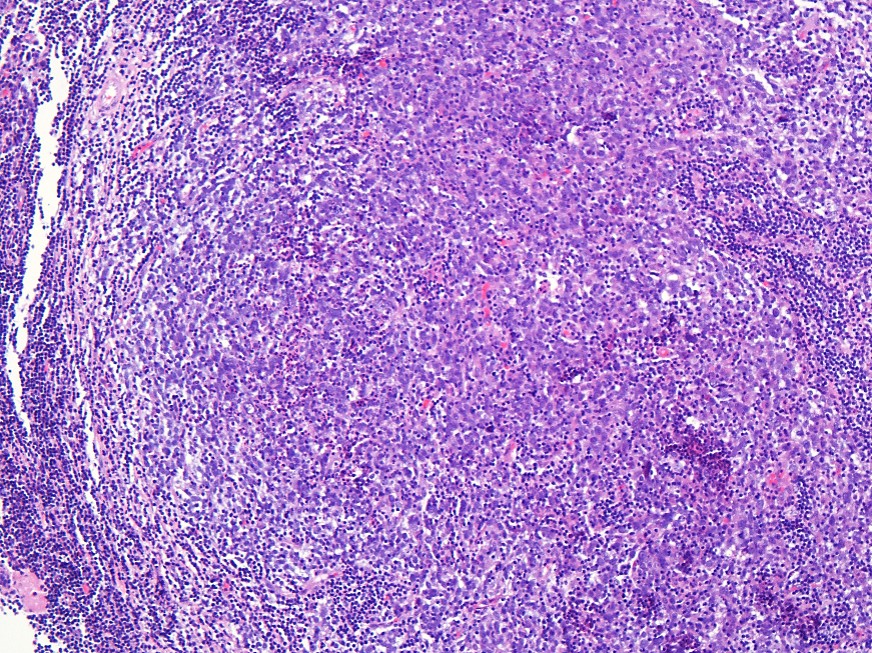

The answer is C, “Follicular dendritic cell sarcoma”.

Follicular dendritic cell sarcoma occurs predominantly in young to middle-aged adults. The majority of cases arise in lymph nodes, but 1/3 can arise in extranodal sites (e.g. GI tract, soft tissue). Local recurrence occurs in up to 50% of cases, and up to 25% of tumors metastasize. Microscopically, tumor cells are spindled to ovoid in shape with an architecture of sheets, fascicles, or storiform whorls. Cells have indistinct borders with eosinophilic cytoplasm. Nuclei have speckled chromatin. Tumors commonly have a lymphocytic infiltrate. On immunohistochemistry, CD21, CD23, and CD35 are positive. Notably, CD45, CD34, keratins, desmin, CD1a, and HMB45 are negative in these tumors.